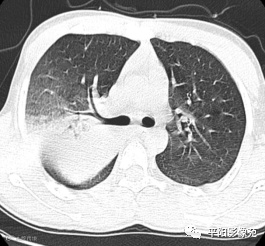

5天后复查X线片及CT:较前加重

影像特征:X线片右肺中上野片状高密度影,下缘以叶间裂为界,上缘及外侧缘模糊;CT位于右肺上叶后段,呈片状实变影,内见支气管影,边缘模糊。

影像诊断:右肺上叶大叶性肺炎。